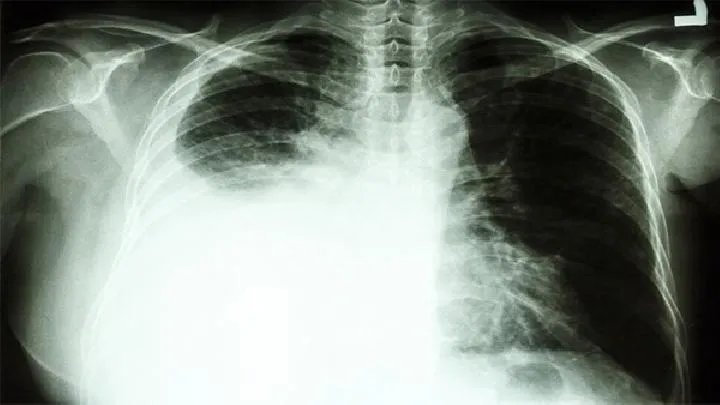

一、免疫正常宿主:急性肺皮炎芽生菌病患者肺部病变广泛,低氧血症严重,应立即给予AMB治疗,但是否所有急性皮炎芽生菌患者都需要治疗还没有定论,因为很多轻度和中度患者不需要治疗就可以自愈。随着安全、高效、低毒的口服抗真菌药物伊曲康唑在临床实践中的应用,现在主张只对急性肺炎患者进行抗真菌药物治疗,首发症状相对较轻,诊断时病情明显好转。

AMB仅用于少数严重患者,包括肺弥漫性浸润、严重中毒症状、严重气体交换障碍和快速传播。对于严重感染,可采用有序治疗。首先使用它AMB临床改善治疗总量为500~1000mg,然后用伊曲康唑治疗6个月。